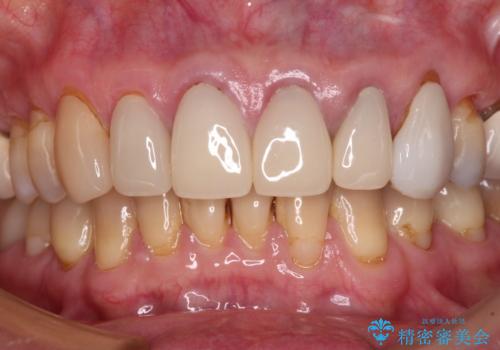

もげてしまった前歯をセラミッククラウンで自然に

- 前歯が土台ごと外れてしまったとのことで来院された患者様です。

土台は外れていましたが破折などの問題はなく、土台からの再治療で対応可能な状態でした。

隣の犬歯も神経が取り除かれていたしたが、ラミネートベニアで治療されており、裏側でむし歯が進行する可能性があったため、こちらも治療が必要と判断されました。

今回の治療を機会に前歯全体をやり直すことも考えたそうですが、取り急ぎ要治療となった2歯を先に治療することとしました。

外れてしまったクラウンを保管しておき、新しいクラウン製作の際に技工所に送ることで、今までと同じような色合いに仕上げることができ、周囲のクラウンとバランスを取ることができます。